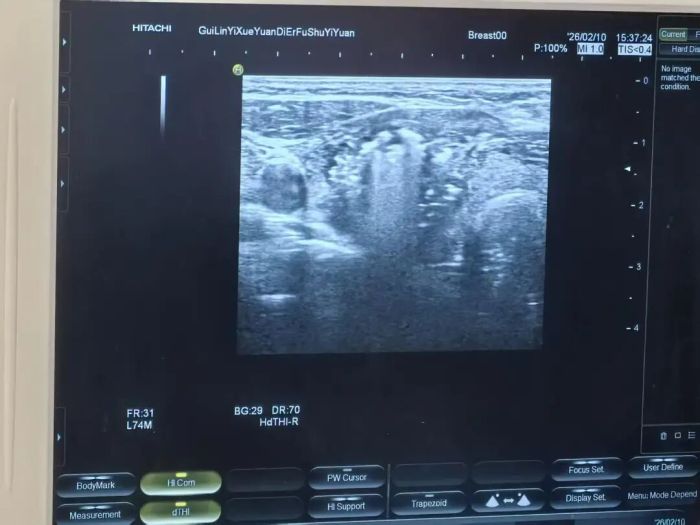

2月10日,乳腺甲状腺外科超声介入室一片忙碌,彩超机、乳腺微创旋切机、甲状腺微波消融仪同时开启,在乳腺甲状腺肿瘤诊疗协作组组长、乳腺甲状腺主任俸瑞发教授亲自主刀下,微创小组高效协作,成功完成了10台微创手术,其中乳腺肿瘤微创旋切活检5台,甲状腺结节微波消融5台,第二天,经过超声复查评估后,这10位患者全都可以出院回家了。

1.术前定位:患者平卧,医生使用超声实时探测,精确确定病灶位置。

3.穿刺旋切:在皮肤上做一个约3-5毫米的微小切口,将旋切针穿刺至病灶处,在超声影像引导下进行多次旋切取样。

皮肤上有一个约1毫米的针孔,消融针在超声引导下精准进入结节内部。启动微波,针尖升温至60-100℃“烧死”病灶,超声上可见强回声覆盖整个结节。消融时间从几分钟到十几分钟不等。

超声造影或彩色多普勒确认结节内已无血流信号,说明消融完全,拔针。